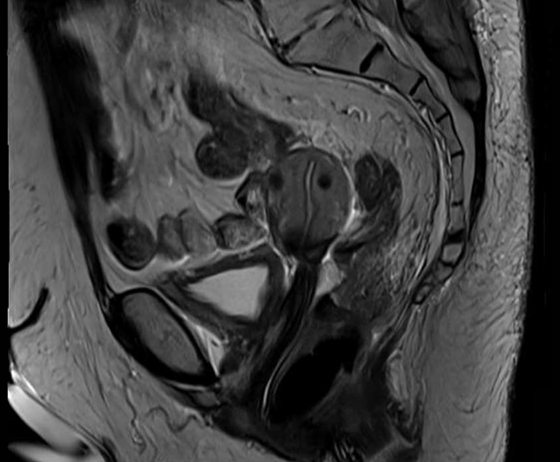

Clinical examination revealed a large fixed cervical mass extending into the upper anterior vaginal wall. MRI demonstrated a large cervical tumour causing cervical stenosis, fluid accumulation within the uterus and indentation of the posterior bladder wall. PET-MRI confirmed a metabolically active central tumour without evidence of nodal disease.

Figure 1: Baseline sagittal T2 MRI showing the presence of a large cervical tumour causing cervical stenosis, uterine fluid accumulation, and posterior bladder indentation